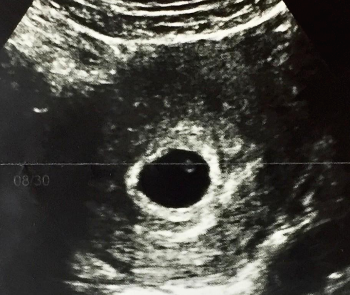

✅ 보통 6주 이후부터 심음이 확인되며, 6-12주 사이의 CRL 길이를 기준으로 임신주수를 정하게 됩니다.

✅ 머리 엉덩 길이 (Crown-Rump Length) : 임신 1분기 아기의 크기를 재는 기준이 됩니다.

아기집 (Gestational Sac, GS)으로도 주수를 추정할 수 있지만 CRL을 사용하는 경향이 있습니다.

✅ 임신 초기의 아기 크기는 CRL로 측정하게 된다.